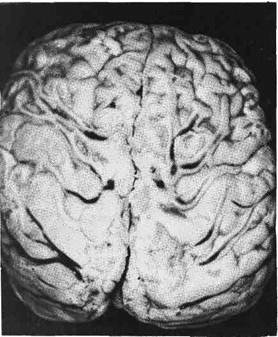

Рис. 401. Менингококковый -менингит.

Гнойное воспаление локализуется преиму-

щественно на поверхности полушарий

большого мозга (по А. В. Цинзерлин-

ГУ).

При менингококков о. м

менингите мягкие мозговые

оболочки в первые сутки от на-

чала болезни становятся резко

полнокровными, они пропитаны

слегка мутноватым серозным экс-

судатом. К концу 2-х и началу

3-х суток экссудат постепенно гус-

теет, приобретает зеленовато-жел-

тый цвет и гнойный характер.

К 5 —6-м суткам он еще более

уплотняется от присоединения

фибринозного выпота. Процесс

начинается с базальной поверх-

ности и переходит по периве-

нозным пространствам на выпук-

лую поверхность преимуществен-

но передних отделов полушарий

большого мозга, располагаясь

здесь в виде желтовато-зеленоватого «чепчика» • или «шапочки» (рис. 401).